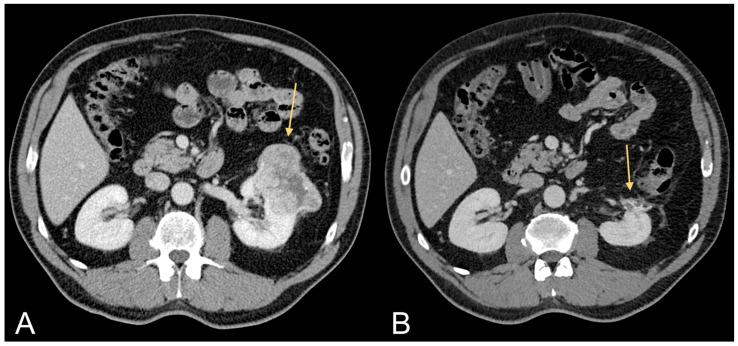

Obesity is an established risk factor for cancer. However, conventional measures like body mass index lack precision in assessing specific tissue quantities, particularly of the two primary abdominal fat compartments, visceral adipose tissue (VAT) and subcutaneous adipose tissue (SAT). Computed tomography (CT) stands as the gold standard for precisely quantifying diverse tissue types. VAT, distinguished by heightened hormonal and metabolic activity, plays a pivotal role in obesity-related tumor development. Excessive VAT is linked to aberrant secretion of adipokines, proinflammatory cytokines, and growth factors, fostering the carcinogenesis of obesity-related tumors. Accurate quantification of abdominal fat compartments is crucial for understanding VAT as an oncological risk factor. The purpose of the present research is to elucidate the role of CT, performed for staging purposes, in assessing VAT (quantity and distribution) as a critical factor in the oncogenesis of obesity-related tumors. In the field of precision medicine, this work takes on considerable importance, as quantifying VAT in oncological patients becomes fundamental in understanding the influence of VAT on cancer development-the potential "phenotypic expression" of excessive VAT accumulation. Previous studies analyzed in this research showed that VAT is a risk factor for clear cell renal cell carcinoma, non-clear cell renal cell carcinoma, prostate cancer, and hepatocarcinoma recurrence. Further studies will need to quantify VAT in other oncological diseases with specific mutations or gene expressions, in order to investigate the relationship of VAT with tumor genomics.

肥胖是一种公认的癌症风险因素。然而,诸如体重指数等传统测量方法在评估特定组织量时缺乏精确性,尤其是对于两个主要的腹部脂肪腔室,即内脏脂肪组织(VAT)和皮下脂肪组织(SAT)。计算机断层扫描(CT)是精确量化各种组织类型的金标准。VAT以其较高的激素和代谢活性为特征,在肥胖相关肿瘤的发展中起关键作用。过多的VAT与脂肪因子、促炎细胞因子和生长因子的异常分泌有关,促进了肥胖相关肿瘤的致癌作用。准确量化腹部脂肪腔室对于理解VAT作为肿瘤学风险因素至关重要。本研究的目的是阐明用于分期目的的CT在评估VAT(数量和分布)作为肥胖相关肿瘤发生的关键因素方面的作用。在精准医学领域,这项工作具有相当重要的意义,因为在肿瘤患者中量化VAT对于理解VAT对癌症发展的影响——过多VAT积累的潜在“表型表达”变得至关重要。本研究分析的先前研究表明,VAT是透明细胞肾细胞癌、非透明细胞肾细胞癌、前列腺癌和肝癌复发的风险因素。进一步的研究需要在具有特定突变或基因表达的其他肿瘤疾病中量化VAT,以便研究VAT与肿瘤基因组学的关系。